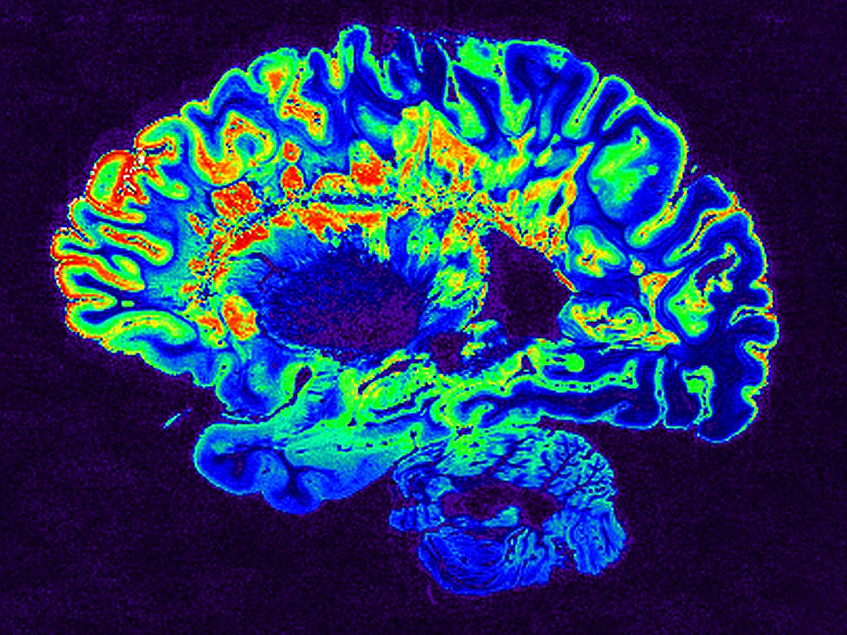

First Gwas For Ms Severity Turns Up First Brain Related Snp Bioworld